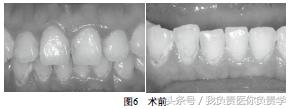

检查:11M,D,12M,D,13M,La,21M,D,22M,31M,D,La,32M,D,La,33M,41M,D,La,42M,D,La,43M,La均不同程度龋坏,质软,黄褐色。冷测正常,叩痛(-),不松动,牙龈无窦道。见图6。